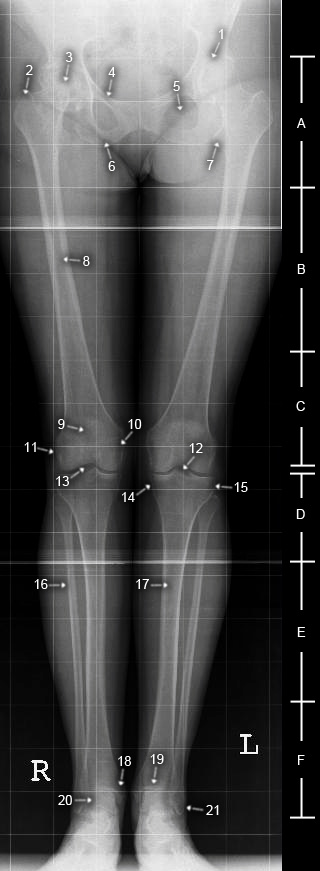

Ganzbeinaufnahme a.p.

A. proximales Femurdrittel

B. mittleres Femurdrittel

C. distales Femurdrittel

D. proximales Unterschenkeldrittel

E. mittleres Unterschenkeldrittel

F. distales Unterschenkeldrittel

1. röntgenologischer Hüftgelenkspalt

2. Trochanter major

3. Caput femoris

4. Os pubis

5. Foramen obturatum

6. Os ischii

7. Trochanter minor

8. Femur

9. Patella

10. Condylus medialis femoris

11. Condylus lateralis femoris

12. Eminentia intercondylaris

13. röntgenologischer Kniegelenkspalt

14. Condylus medialis tibiae

15. Condylus lateralis tibiae

16. Fibula

17. Tibia

18. Malleolus medialis

19. Articulatio talocruralis

20. Trochlea tali

21. Malleolus lateralis